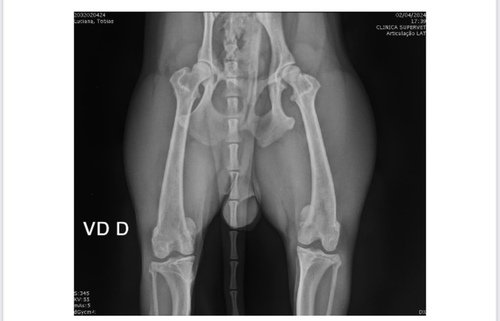

Gente esse meu cachorrinho tem 10 meses está com um problema muito sério, ele esta com desvio medial de patelas esquerda e direita em relação ao respectivo sulco troclear, sugerindo com severa luxação de patelas.

Segue o raio X